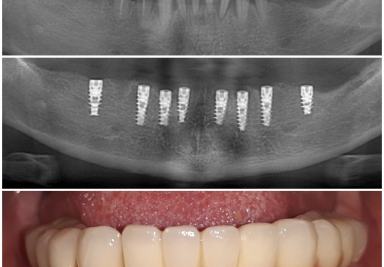

Full mouth rehabilitation with dental implants

Full mouth rehabilitation with dental implants and fixed ceramic crowns

Mandibular dental implants

Mandibular dental implants and screw-retained metal-based porcelain crowns